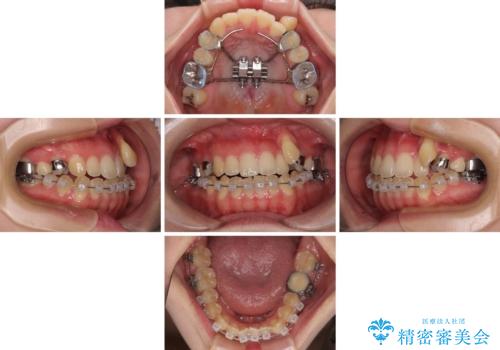

急速拡大装置 狭い上顎骨を拡大してワイヤー装置で八重歯を短期間治療

- 上顎の八重歯やデコボコを気にして来院された患者様です。

上顎歯列が狭窄していたため、急速拡大装置により上顎骨を側方に拡大しながら、ワイヤー装置にて矯正治療を行うこととしました。

上顎骨を拡大することで、八重歯やデコボコを歯列に収めることができ、下顎の歯が外に位置していた奥歯の咬み合わせも改善することができました。